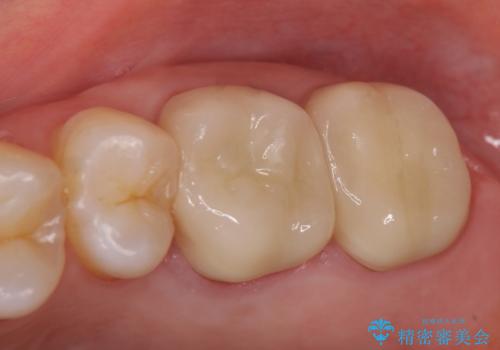

オールセラミッククラウンについて

今回用いたオールセラミッククラウンはジルコニアフレームという白い素材の上にセラミックを盛っているため、審美性が非常に高いのが特徴です。

また、ジルコニアは人工ダイヤモンドの材料にも使われているほど高い強度を持っており、そのためオールセラミッククラウンは審美性だけでなく、奥歯やブリッジの補綴も可能とするクラウンです。